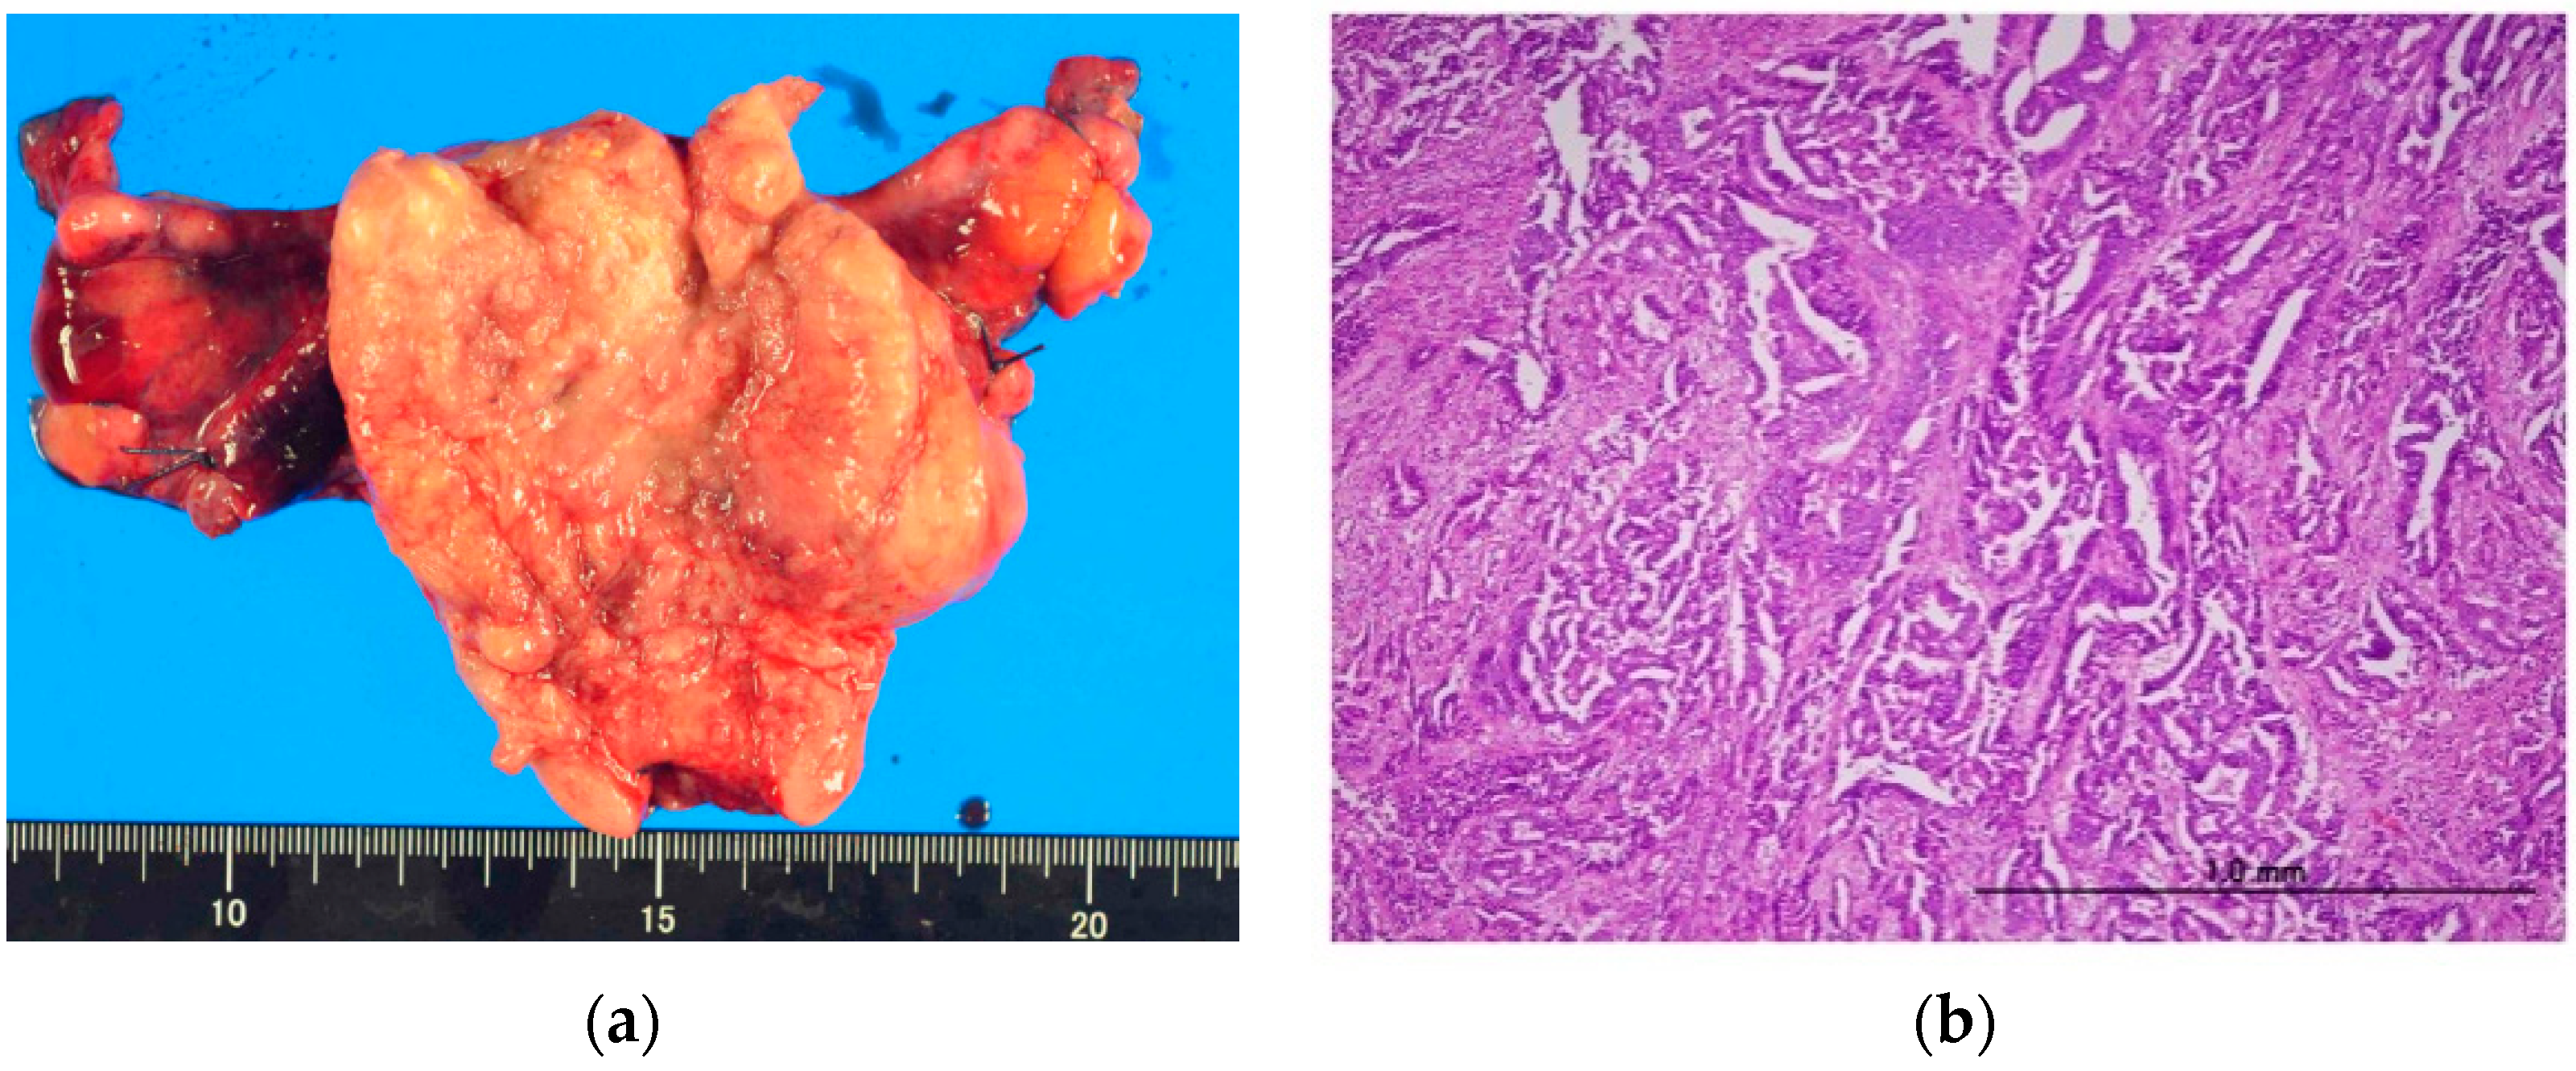

2. Case Presentation